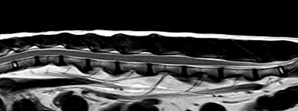

연구 대상은 4세 장모 고양이로 갑작스러운 좌측 후지 절뚝거림과 점프 회피 증상을 보였다. MRI 검사 결과, L6–L7 추간판이 원외측으로 탈출해 신경근을 압박하고, 국소 염증을 동반한 사실이 밝혀졌다. 이는 지금까지 개에서만 드물게 보고된 질환으로 고양이에서는 최초 사례다.